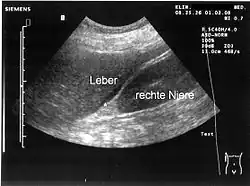

Sonografie

Die Ultraschalluntersuchung des Bauches erbringt meist freie Flüssigkeit und/oder freie Luft in der Bauchhöhle. Sichtbar wird hierbei auch die verminderte Motilität (Eigenbewegung) des Darmes. In vielen Fällen gelingt es, mit der Sonografie die Ursache der Peritonitis (Gallenblasenperforation, Dickdarmmileus mit Perforation, Pankreatitis etc.) einzugrenzen.